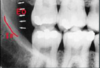

identify the anatomical structure below.

mandibular canal

104

internal oblique ridge (line)

105

external oblique ridge (line)

106

submandibular fossa

107

coronoid process